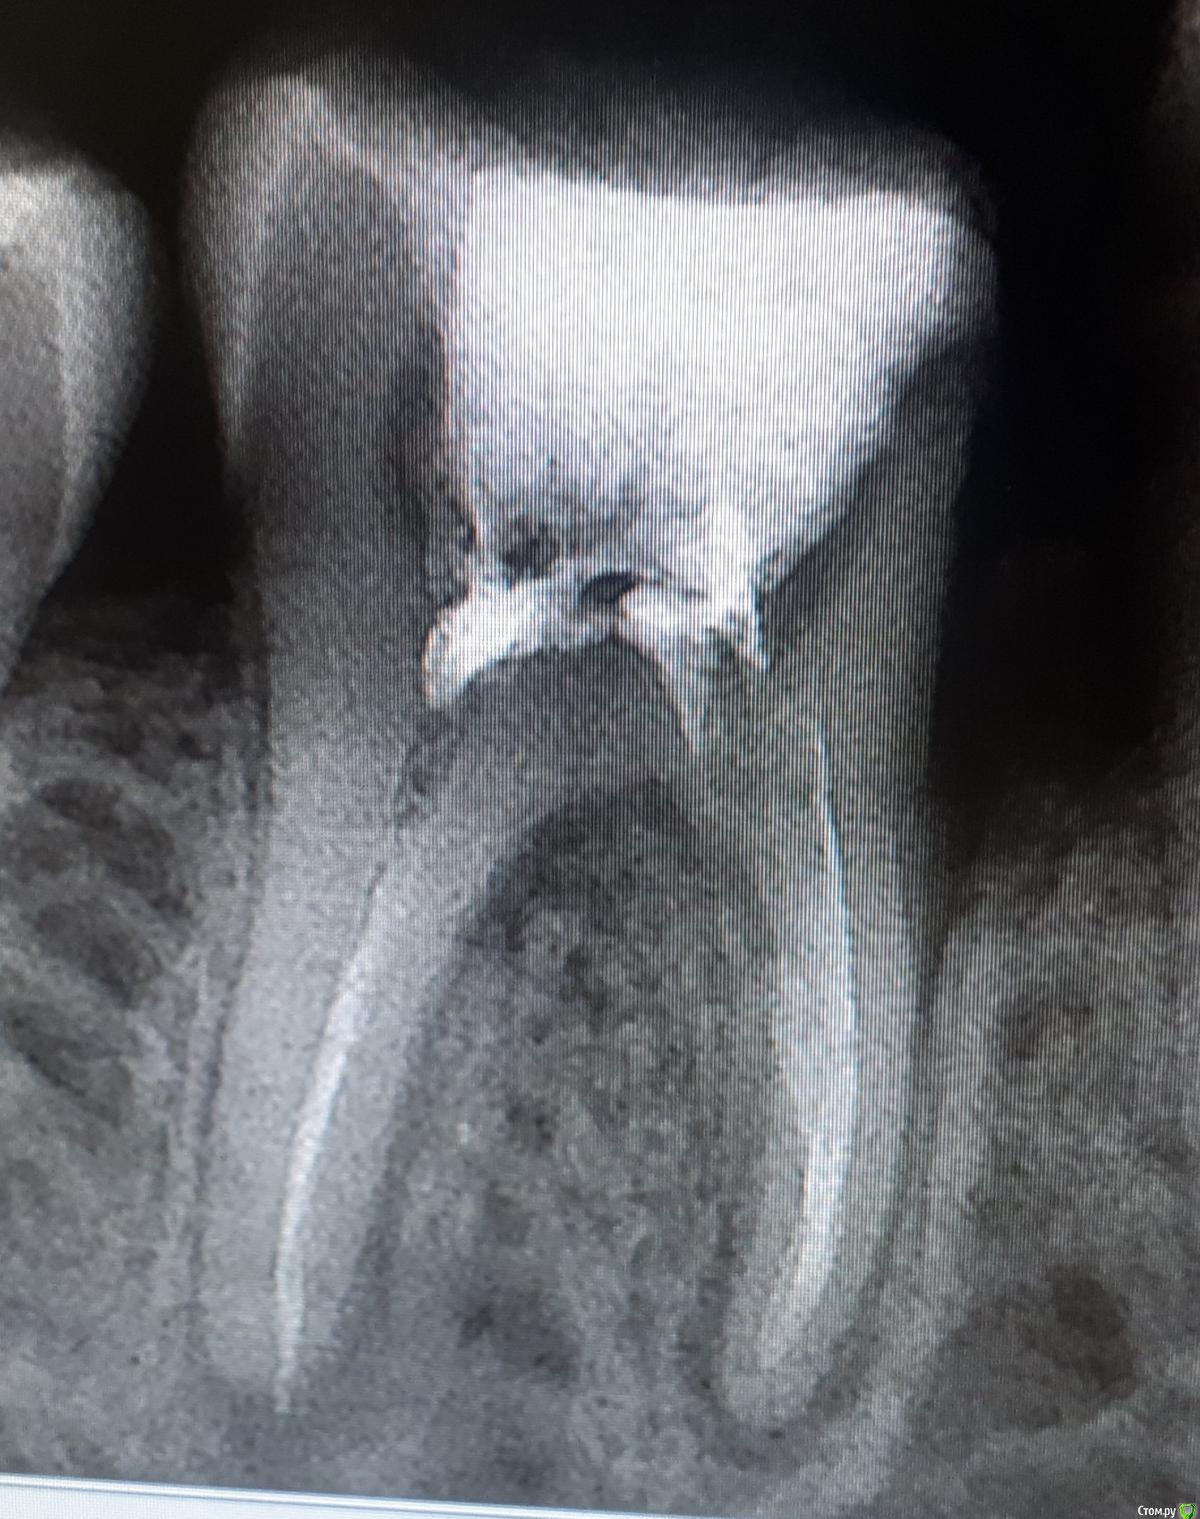

Посмотрите, пожалуйста, снимки.

Также первый врач сказала что после лечения (депульпирования- приложено фото - более светлое) на зуб надо ставить коронку - ортодонт отказалась ставить коронку т.к. один канал не пройден до конца.

PS 2 снимка - на первом зуб с запломбированными каналами во время попадания инфекции и разбухания десны (июль)

На более тёмном снимке зуб с перелеченными каналами при наложении "десенной повязки"